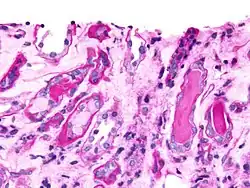

- Cilindros epiteliales

Estos cilindros se forman por inclusión o adhesión de células epiteliales descamadas del revestimiento tubular. Estas células pueden adherirse en orden aleatorio o en hojas que son distinguidas por núcleos grandes, redondos y una baja cantidad de citoplasma. Se los puede ver en casos de necrosis tubular aguda e ingestión de tóxicos (mercurio, dietilenglicol, salicilatos, etc.). En cada caso hojas o grupos de células pueden “mudar” simultáneamente según la focalidad de la lesión. El citomegalovirus y el virus de la hepatitis también son microorganismos que pueden causar la muerte de las células epiteliales.